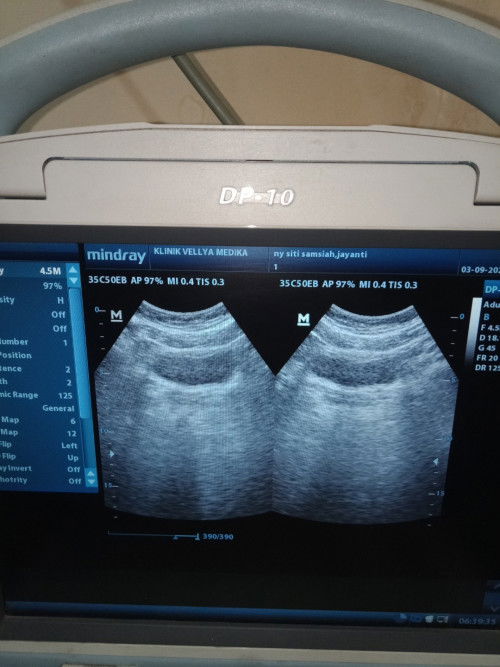

Bun pas awal agustus aku tespek dua garis samar, di barengin keram perut bawah, terus di tespek lagi malah garis satu keram nya gak ilang² sampe akhir agustus terus tgl 22 agustus flek 3 hari. Kemarin pas tgl 3 september di usg kata dokternya udah Ada kantung nya. Kira² kenapa ya tespek aku gak pernah garis dua tebal? Pas hamil pertama juga kayak gitu sering garis satu pas di usg udah hamil #Sharing_dong_Bund #bantujawab